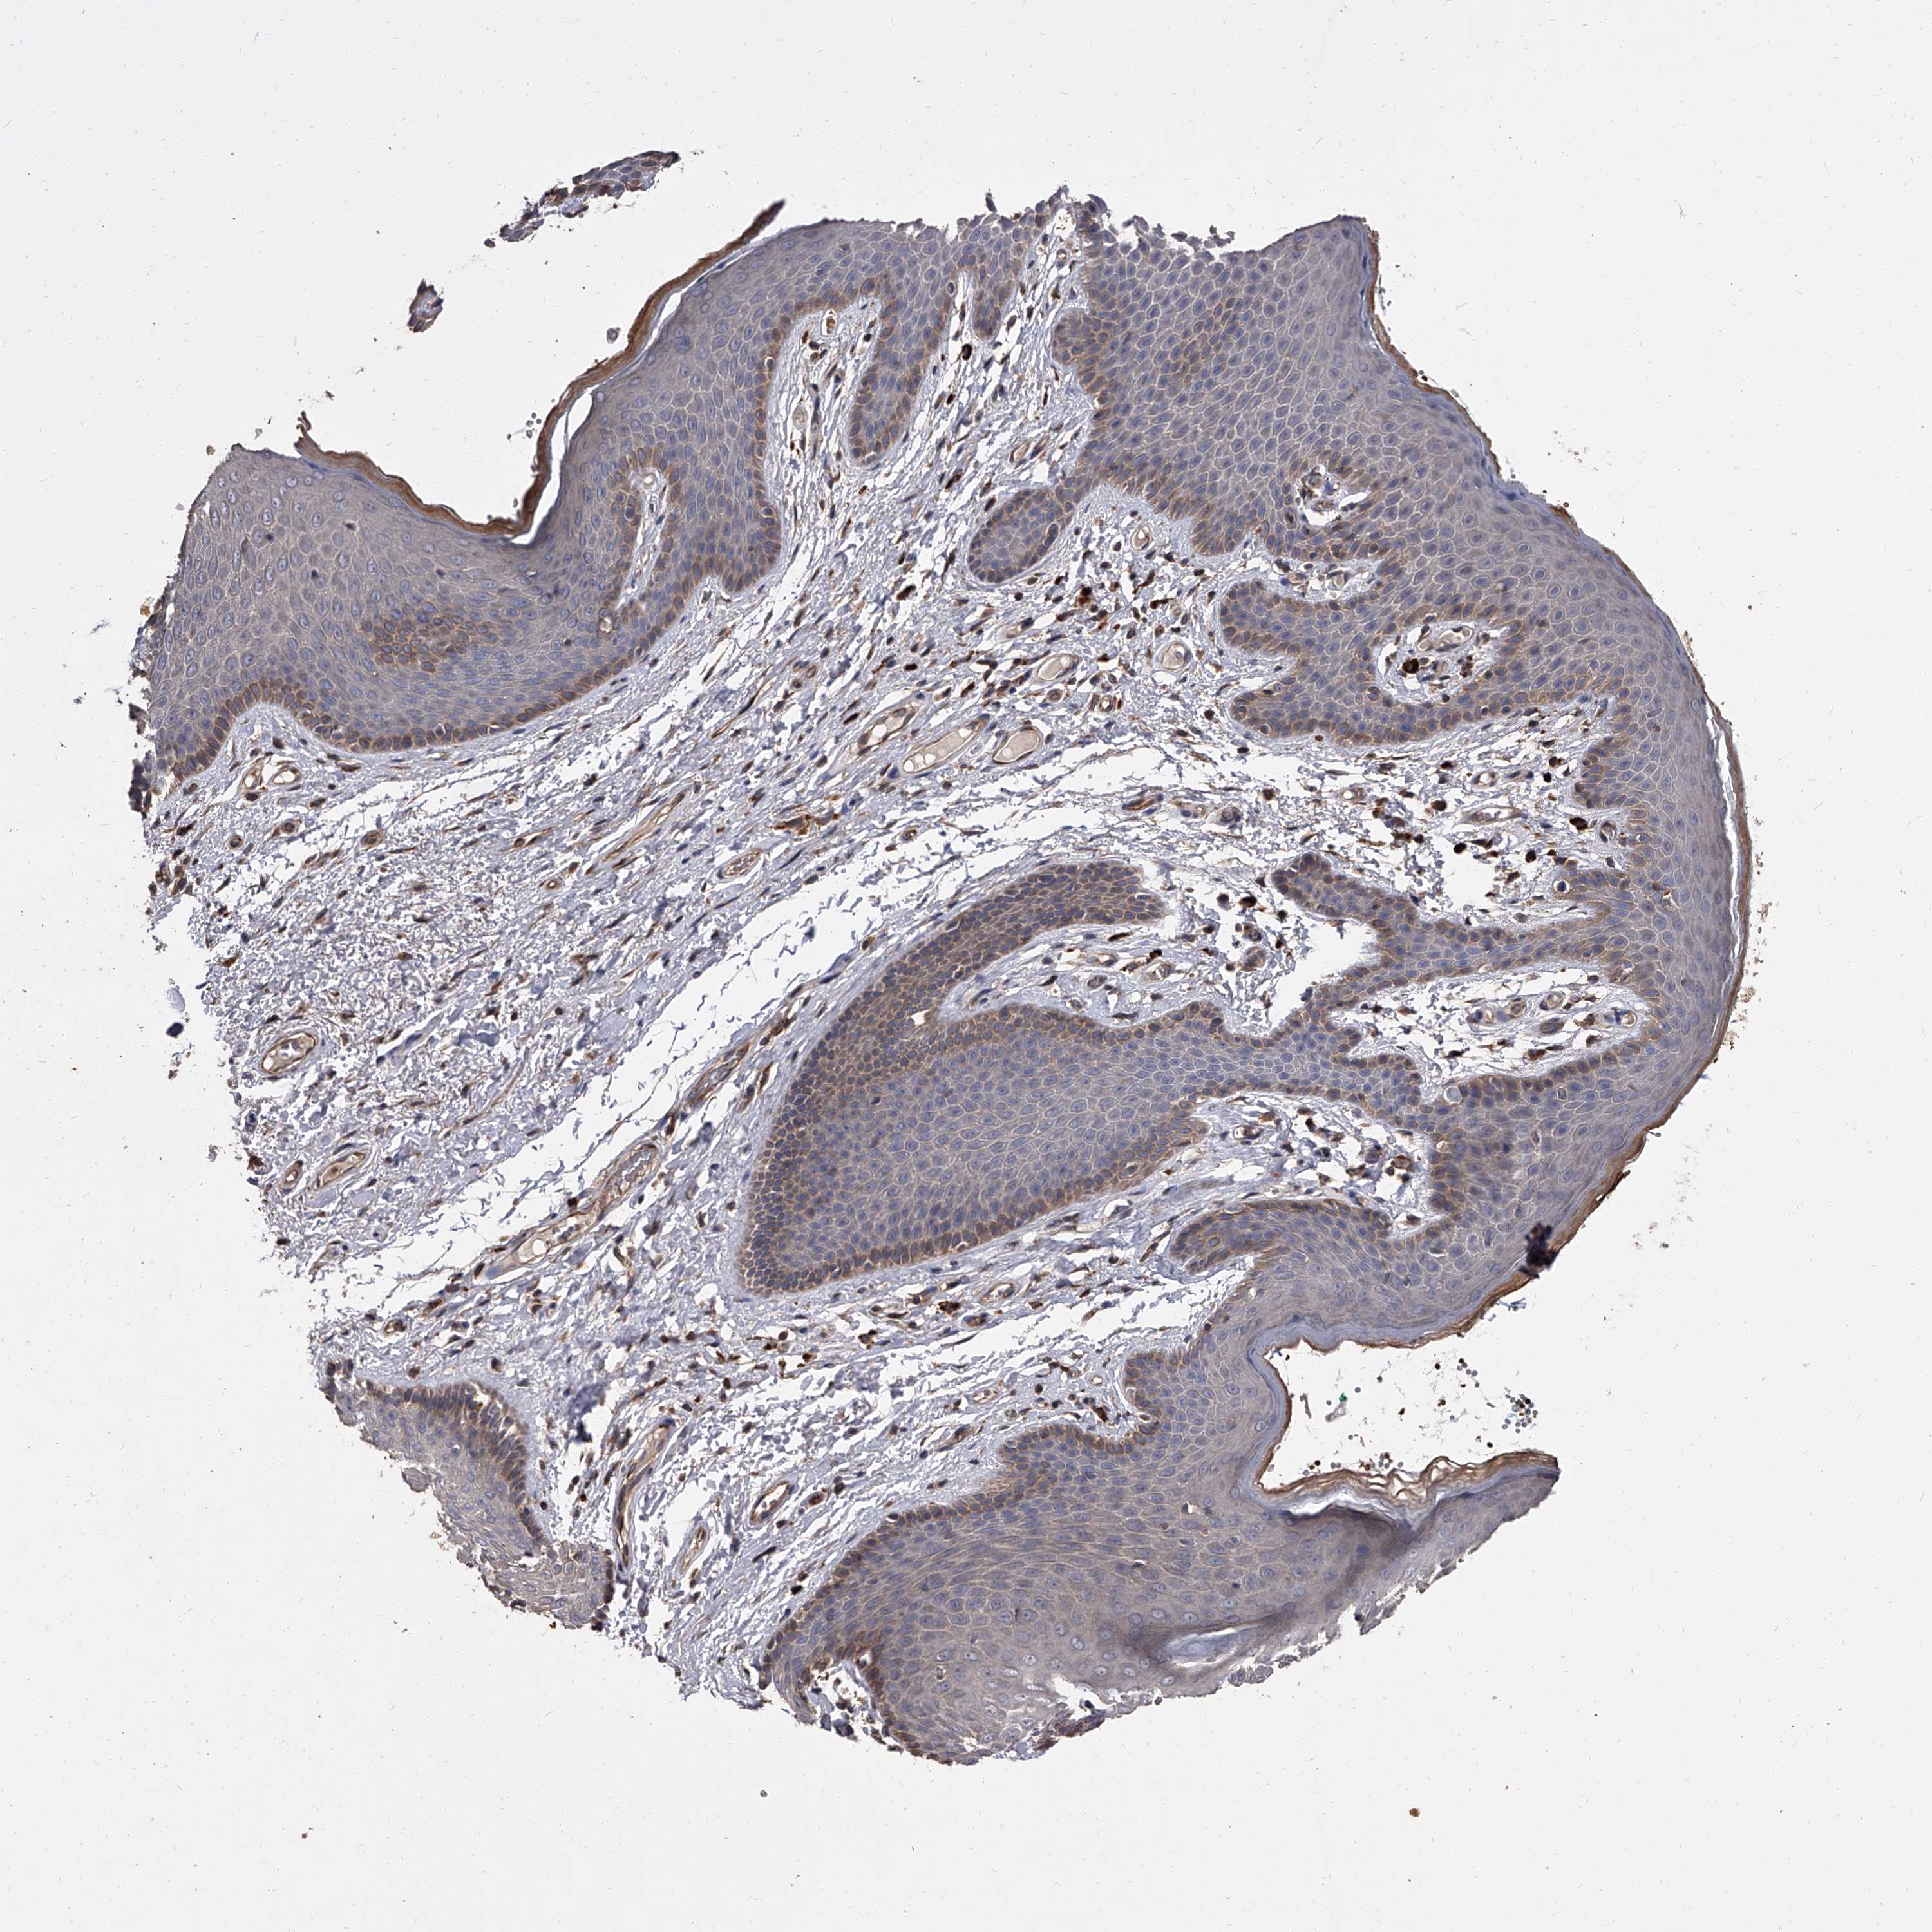

SKIN 1 - Antibody stainingi

Antibody staining in the annotated cell types in the current human tissue is reported as not detected, low, medium, or high, based on conventional immunohistochemistry profiling in selected tissues. This score is based on the combination of the staining intensity and fraction of stained cells.

Each image is clickable and will lead to virtual microscopy that enables deeper exploration of all samples and also displays staining intensity scores, fraction scores and subcellular localization as well as patient and tissue information for each sample.

Antibody HPA027409Antibody HPA027453Antibody HPA030058

Langerhans MediumMediumNot detected

Fibroblasts HighMediumMedium

Keratinocytes HighMediumMedium

Melanocytes MediumMediumMedium